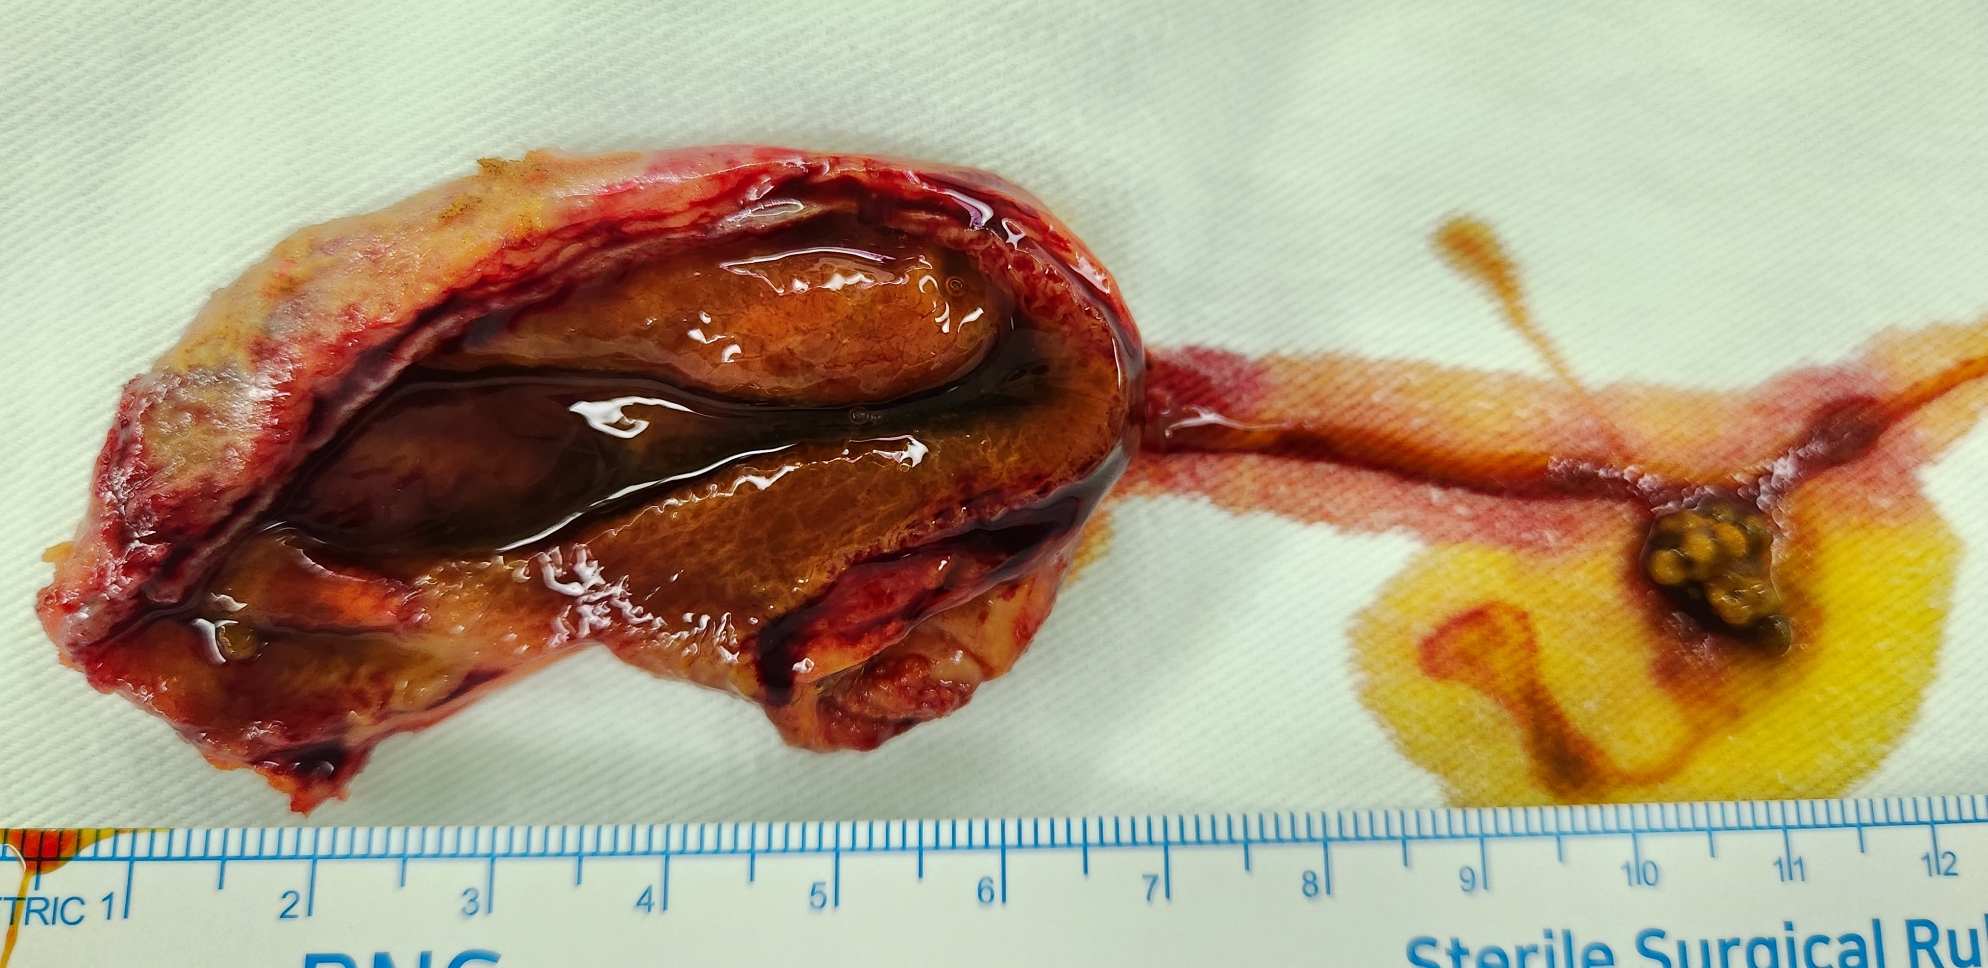

소화불량 및 명치 통증으로 타병원에서 초음파 시행후 담석 담낭염으로 수술 위해 제 외래로 오셨던 분입니다.

방금 단일공 복강경 담낭절제술을 시행했습니다.

수술은 25분 걸렸습니다.